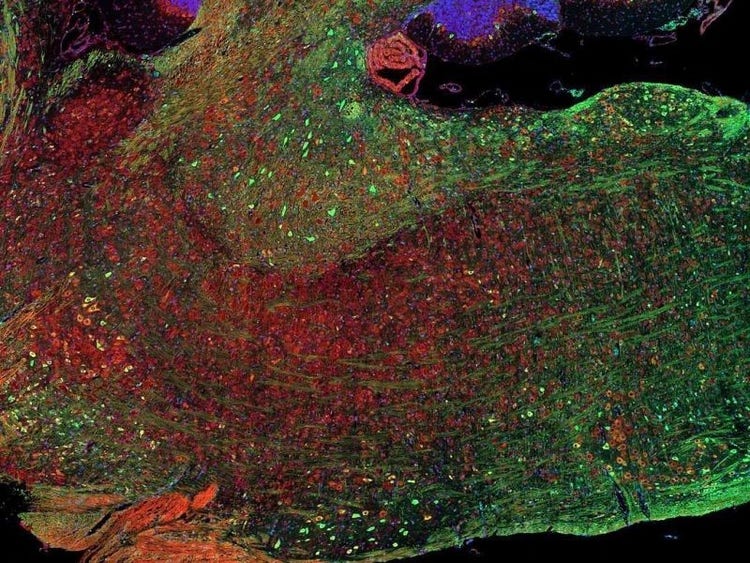

Fluorescence imaging of a mouse brain

Jedes dieser Bilder sieht aus der Nähe anders aus, aber sie fügen sich zu einem Bild eines Mäusegehirns zusammen, das mit Fluoreszenzbildgebung aufgenommen wurde.

Der britische Wissenschaftler Sir George G. Stokes beobachtete zum ersten Mal, dass das Mineral Flussspat fluoresziert, wenn es mit ultraviolettem Licht beleuchtet wird, und prägte den Begriff „Fluoreszenz“. Stokes fand heraus, dass das fluoreszierende Licht eine größere Wellenlänge hat als das Anregungslicht, ein Phänomen, das heute als Stokes-Verschiebung bekannt ist. Die Fluoreszenzmikroskopie ist eine hervorragende Methode zur Untersuchung von Materialien, die entweder in ihrer natürlichen Form (Primär- oder Autofluoreszenz) oder nach Behandlung mit fluoreszierenden Chemikalien (Sekundärfluoreszenz) fluoreszieren können.